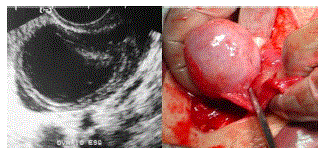

Paciente do sexo feminino com dor importante e incapacitante no baixo ventre de início súbito. Realizou exame ultrassonográfico que demonstrou:

enunciado 1829646-1

Baseado nas imagens disponibilizadas, qual o seu diagnóstico?